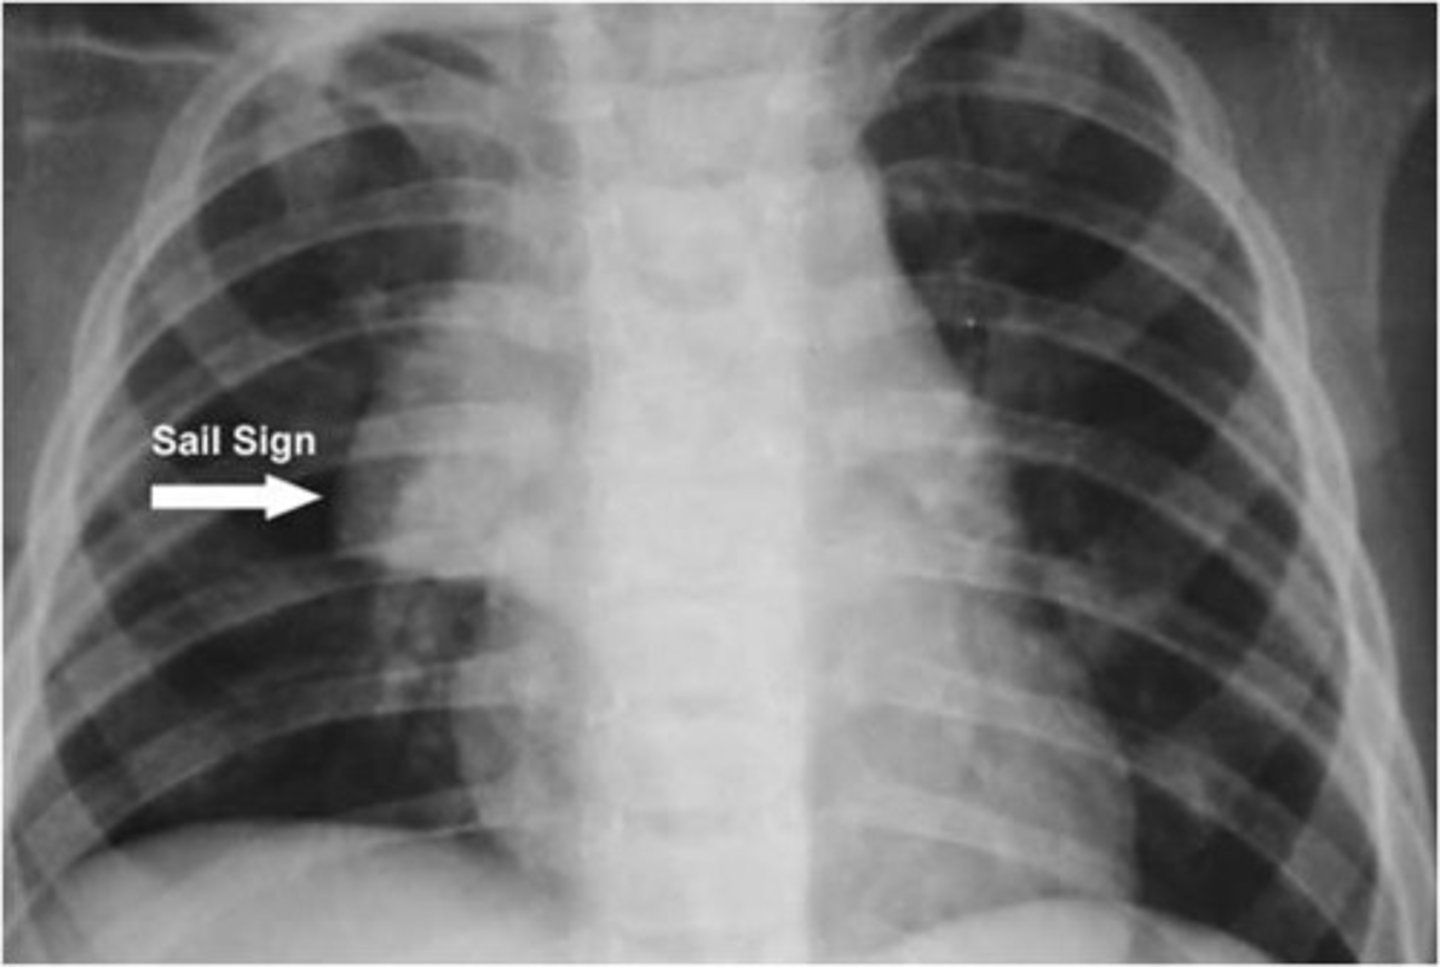

"sail sign" noted child x-ray < 3 years. What can this be?

Thymus

- triangular shape, scalloped border, uniform density

- anterior mediastinum behind sternum + front of the heart, aortic arch, trachea